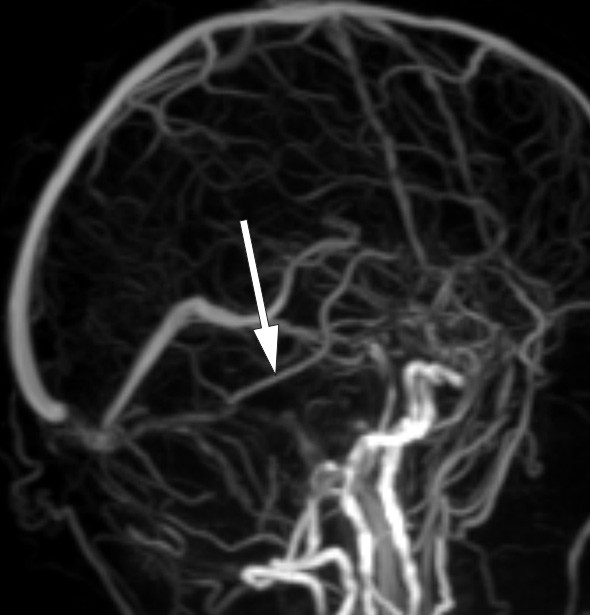

Cerebral CT yielded no definitive findings, but raised suspicion of intracranial venous pathology. T1-weighted MRI of the posterior cranial fossa after contrast injection revealed a thrombus in the right transverse sinus (Fig. 1), but no obstruction on the left side.

Figure 1  Thrombus in right transverse sinus (arrow) on T1-weighted MRI after contrast injection

A small number of cases that have been examined anatomically and with CT or MRI scans indicate that prosopagnosia is usually associated with bilateral medial occipitotemporal lesions. There are also rare cases caused by unilateral injury, almost always on the right side (14). Our patient’s thrombus was in fact in the right transverse sinus (Fig. 1). Venous drainage from the temporal lobe into the transverse sinus occurs via the vein of Labbé (inferior anastomotic vein), and venous stasis here can cause circulatory disturbances in associated brain tissue. MRI revealed no diffusion abnormalities or other parenchymal changes. However, no signal was detected in the vein of Labbé on the side in question, whereas a good signal was obtained in the contralateral vein (Fig. 3). On balance, we consider it likely that the MRI findings are related to the patient’s cognitive symptoms.